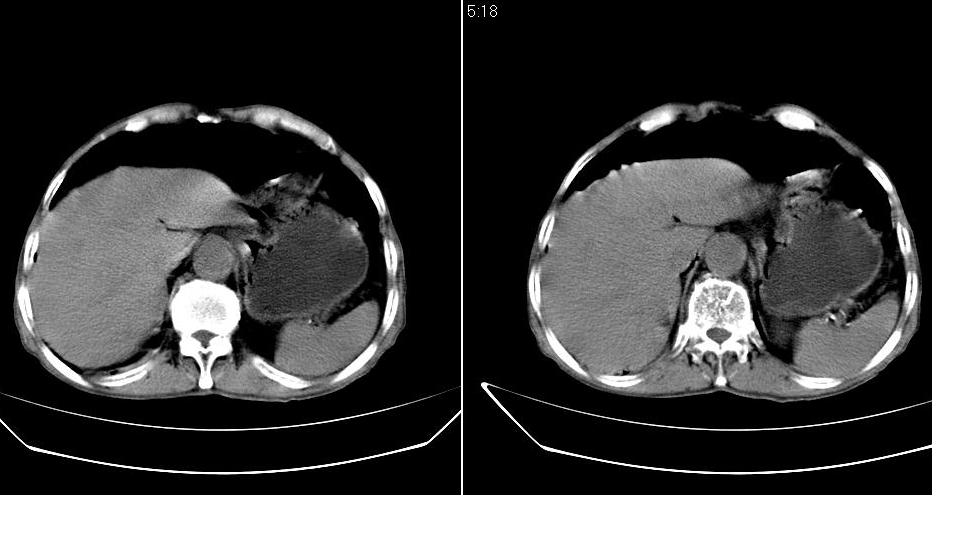

男,76岁,上腹部疼二天来就诊,彩超提示肝左叶占位,随后做上腹部ct平扫,今天做上腹部ct增强扫描,手工推药,效果不好,请谅解。

肝左叶s4肿块强化形式大概是:慢进慢出,逐渐强化----考虑血管瘤/腺瘤?{动脉期应更提前扫}。

肝内胆管积气扩张,胆囊增大,肝右前叶低密度灶,逐渐强化,一元论,胆系感染,局限性肝脓肿;右肾囊肿。

考虑肝s4段肝脓肿可能?未排除肝癌。右肾上极囊肿。